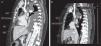

In view of the findings, a chest tube was placed and the patient began a specific protein-rich, low-fat diet, with supplements of medium-chain triglycerides and exclusion of long-chain triglycerides. Chest computed tomography (CT) (Fig. 1) showed thrombosis of the superior vena cava from the mouth of the azygos vein to its entry into the right atrium, so the implanted vascular reservoir was removed. The patient was also evaluated by the hemostasis and peripheral vascular surgery units, and anticoagulation for at least 3 months was recommended, initially with low molecular weight heparin and later with acenocumarol. The patient progressed well during admission and was discharged with anticoagulant treatment and specific dietary recommendations for chylothorax. Initial clinical and radiological progress was good, so a normal diet was reinstated.

(A) Computed tomography with intravenous contrast in the venous phase. Sagittal slice. A superior vena cava filling defect is visualized proximal to the mouth of the arch of the azygos vein, extending to the entry into right atrium, consistent with at least partial thrombosis of the structure, and associated with significant effusion. (B) Sagittal slice. Distal tip of the subcutaneous reservoir in relation to the subcutaneous vena cava thrombosis. IVC: inferior vena cava; RA: right atrium; sc: subcutaneous; SVC: superior vena cava.